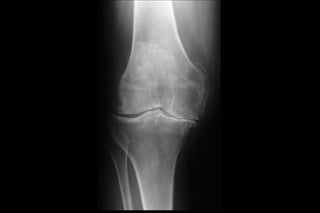

SEVERE OSTEOARTHRITIS

OF THE KNEE

• MRI report –ACL tear – Macerated, complex tear of the medial meniscus – Complex tear of the lateral meniscus – Signal change in the MCL consistent with partial tear – Subchondral bone edema and cysts – Ganglion cyst adjacent to the PCL – Large popliteal cyst – Multiple intra-articular bodies – Large joint effusion – Diffuse synovial hypertrophy SEVERE OSTEOARTHRITIS OF THE KNEE